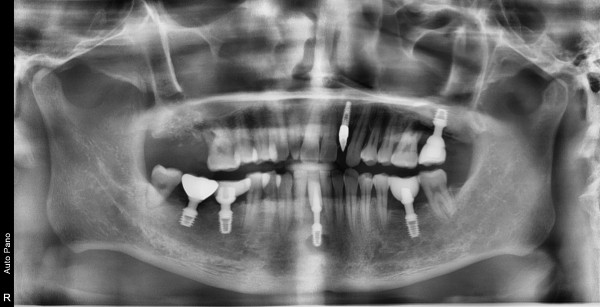

44세 남자 상악 구치부 뼈 이식후 임플란트 식립